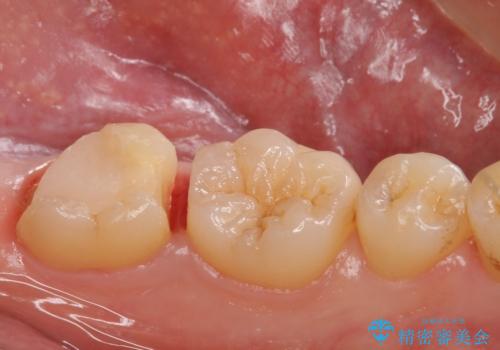

他院で入れたセラミックインレーが取れた。

- 他院で入れたセラミックの詰め物が取れてしまい来院。

適合を確認したところ、不適合だったため新しく形を作り直して、型取りをした方が良いことを説明した。

セラミックの詰め物で治療すると、詰め物の範囲が大きくなり、割れてしまう可能性があるので以下の治療の提案をした。